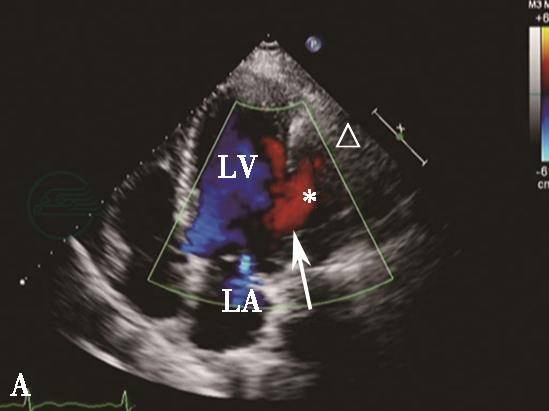

图5心肌梗死后左心室游离壁破裂合并假性室壁瘤形成彩色多普勒血流图像

A.彩色多普勒血流图像显示收缩期血流通过左心室侧壁破口(箭头示)进入假性室壁瘤(星号示);B.舒张期血流自假性室壁瘤返回左心室,瘤体内可见附壁血栓(三角示)。LA.左心房;LV.左心室。